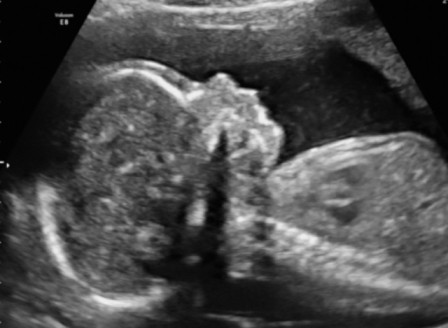

najpierw cesarke sama wymusilam, ale po ostatnim usg, gdy okazalo sie sie, ze chlopiec jest duzo wiekszy od dziewczynki, a jest jako twin 2, to ze wskazania mam cesarke, zeby nie bylo komplikacji